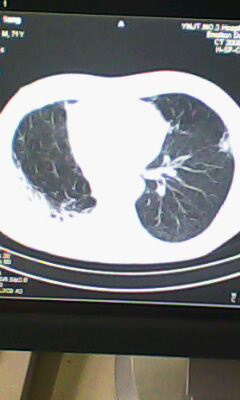

标题: CT25675:男 71 肺癌部分切除术后 3年 [打印本页]

标题: CT25675:男 71 肺癌部分切除术后 3年

两肺感染性病变,右侧肺膨胀不全,左侧上叶结节影及左侧颈部淋巴结肿大建议复查。

1)两肺感染性病变。2)右侧胸膜增厚。3)冠状动脉及主动脉钙化。

右肺炎症,左肺炎症。

两肺感染性病变\\右侧胸膜增厚

术后改变,双肺内纤维索条影考虑与放疗有关。